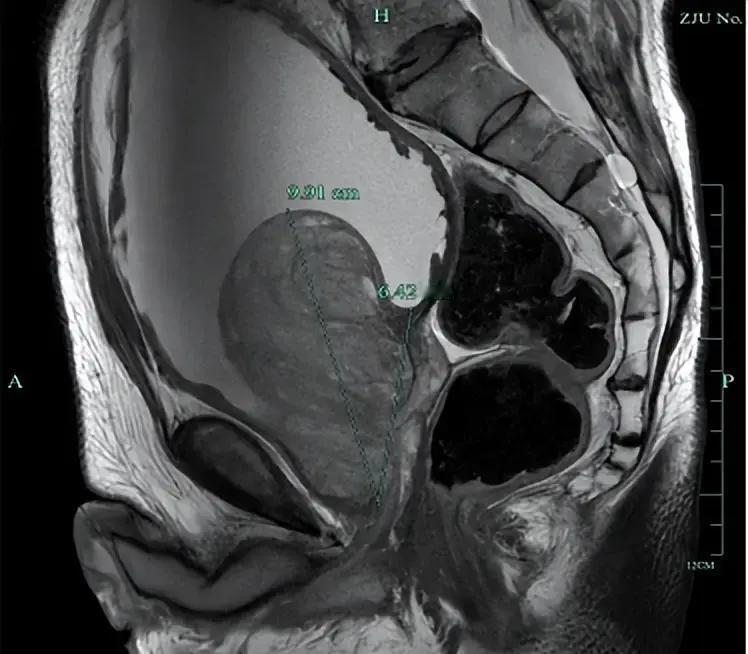

前列腺体积9.2×6.8×6.3cm³,杨大爷忍痛十几年,高血压血脂脑梗心衰缠身,排尿堵塞直接伤肾。PSA升27.7,经活检确认纯增生炎症。当地医院直言风险爆表,手术易出血漏尿肾衰,劝死扛。